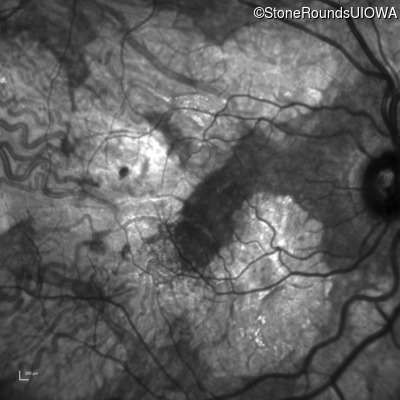

Infrared Fundus Photograph - Right - 20/20 -3

Exemplar

Infrared Fundus Photograph - Left - 20/40 +2